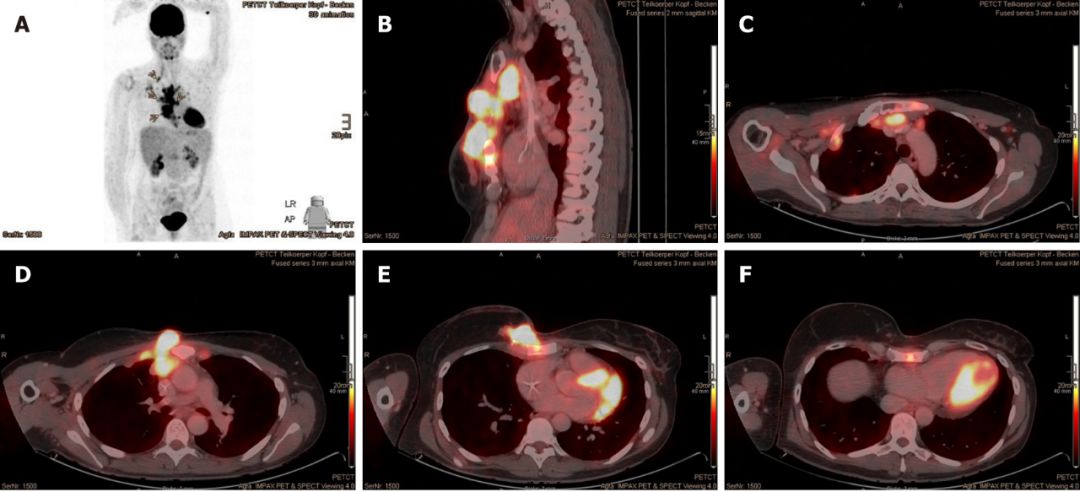

2015年7月,CT扫描发现肿瘤已经侵入肋软骨和腹侧胸膜,她的癌症全面复发了。

这时,Mary已经没有更多的选择,为了降低体内雌激素水平,她切除了双侧卵巢,然后参加了一项氟维司群联合ribociclib的临床试验。2016年2月,由于病情进展,她退出了试验,右侧胸骨的病灶已经达到了30 mm×50 mm×20 mm。

2016年11月至12月,Mary接受了右侧胸骨肿瘤以及邻近胸膜,右侧腋窝,胸骨旁和纵隔区域的淋巴结转移的质子放疗。

01治疗前

幸运的是,Mary对质子治疗的耐受性很好,仅出现了轻微的咳嗽和反流。由于对肺部有一定的辐射剂量,她吃了一些环丙沙星预防放射性肺炎的发生。随后的检查结果显示,癌细胞终于耐不住质子的强烈攻击,开始节节败退,病灶在一次次的缩小。

在最近一次CT扫描中,仍然没有发现肿瘤进展迹象。为了预防病情进展,Mary现在继续使用来曲唑和denosumab进行全身治疗。